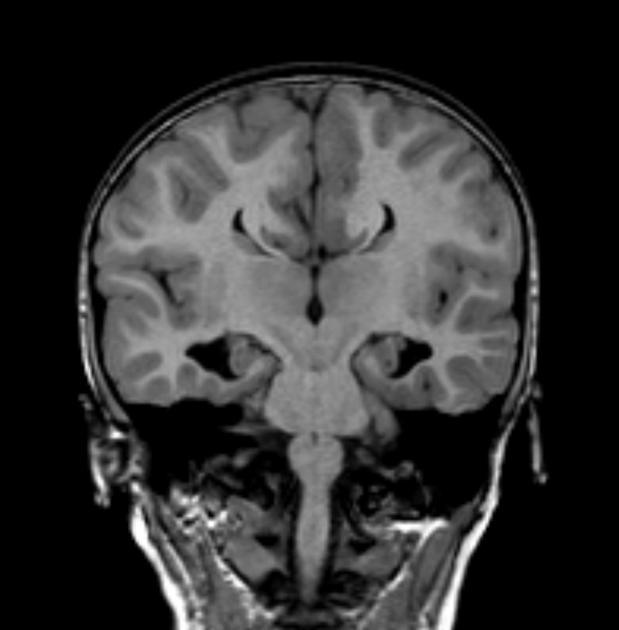

Diagnosis?

Chiari II.

Findings on antenatal ultrasound: banana cerebellum sign, lemon sign.